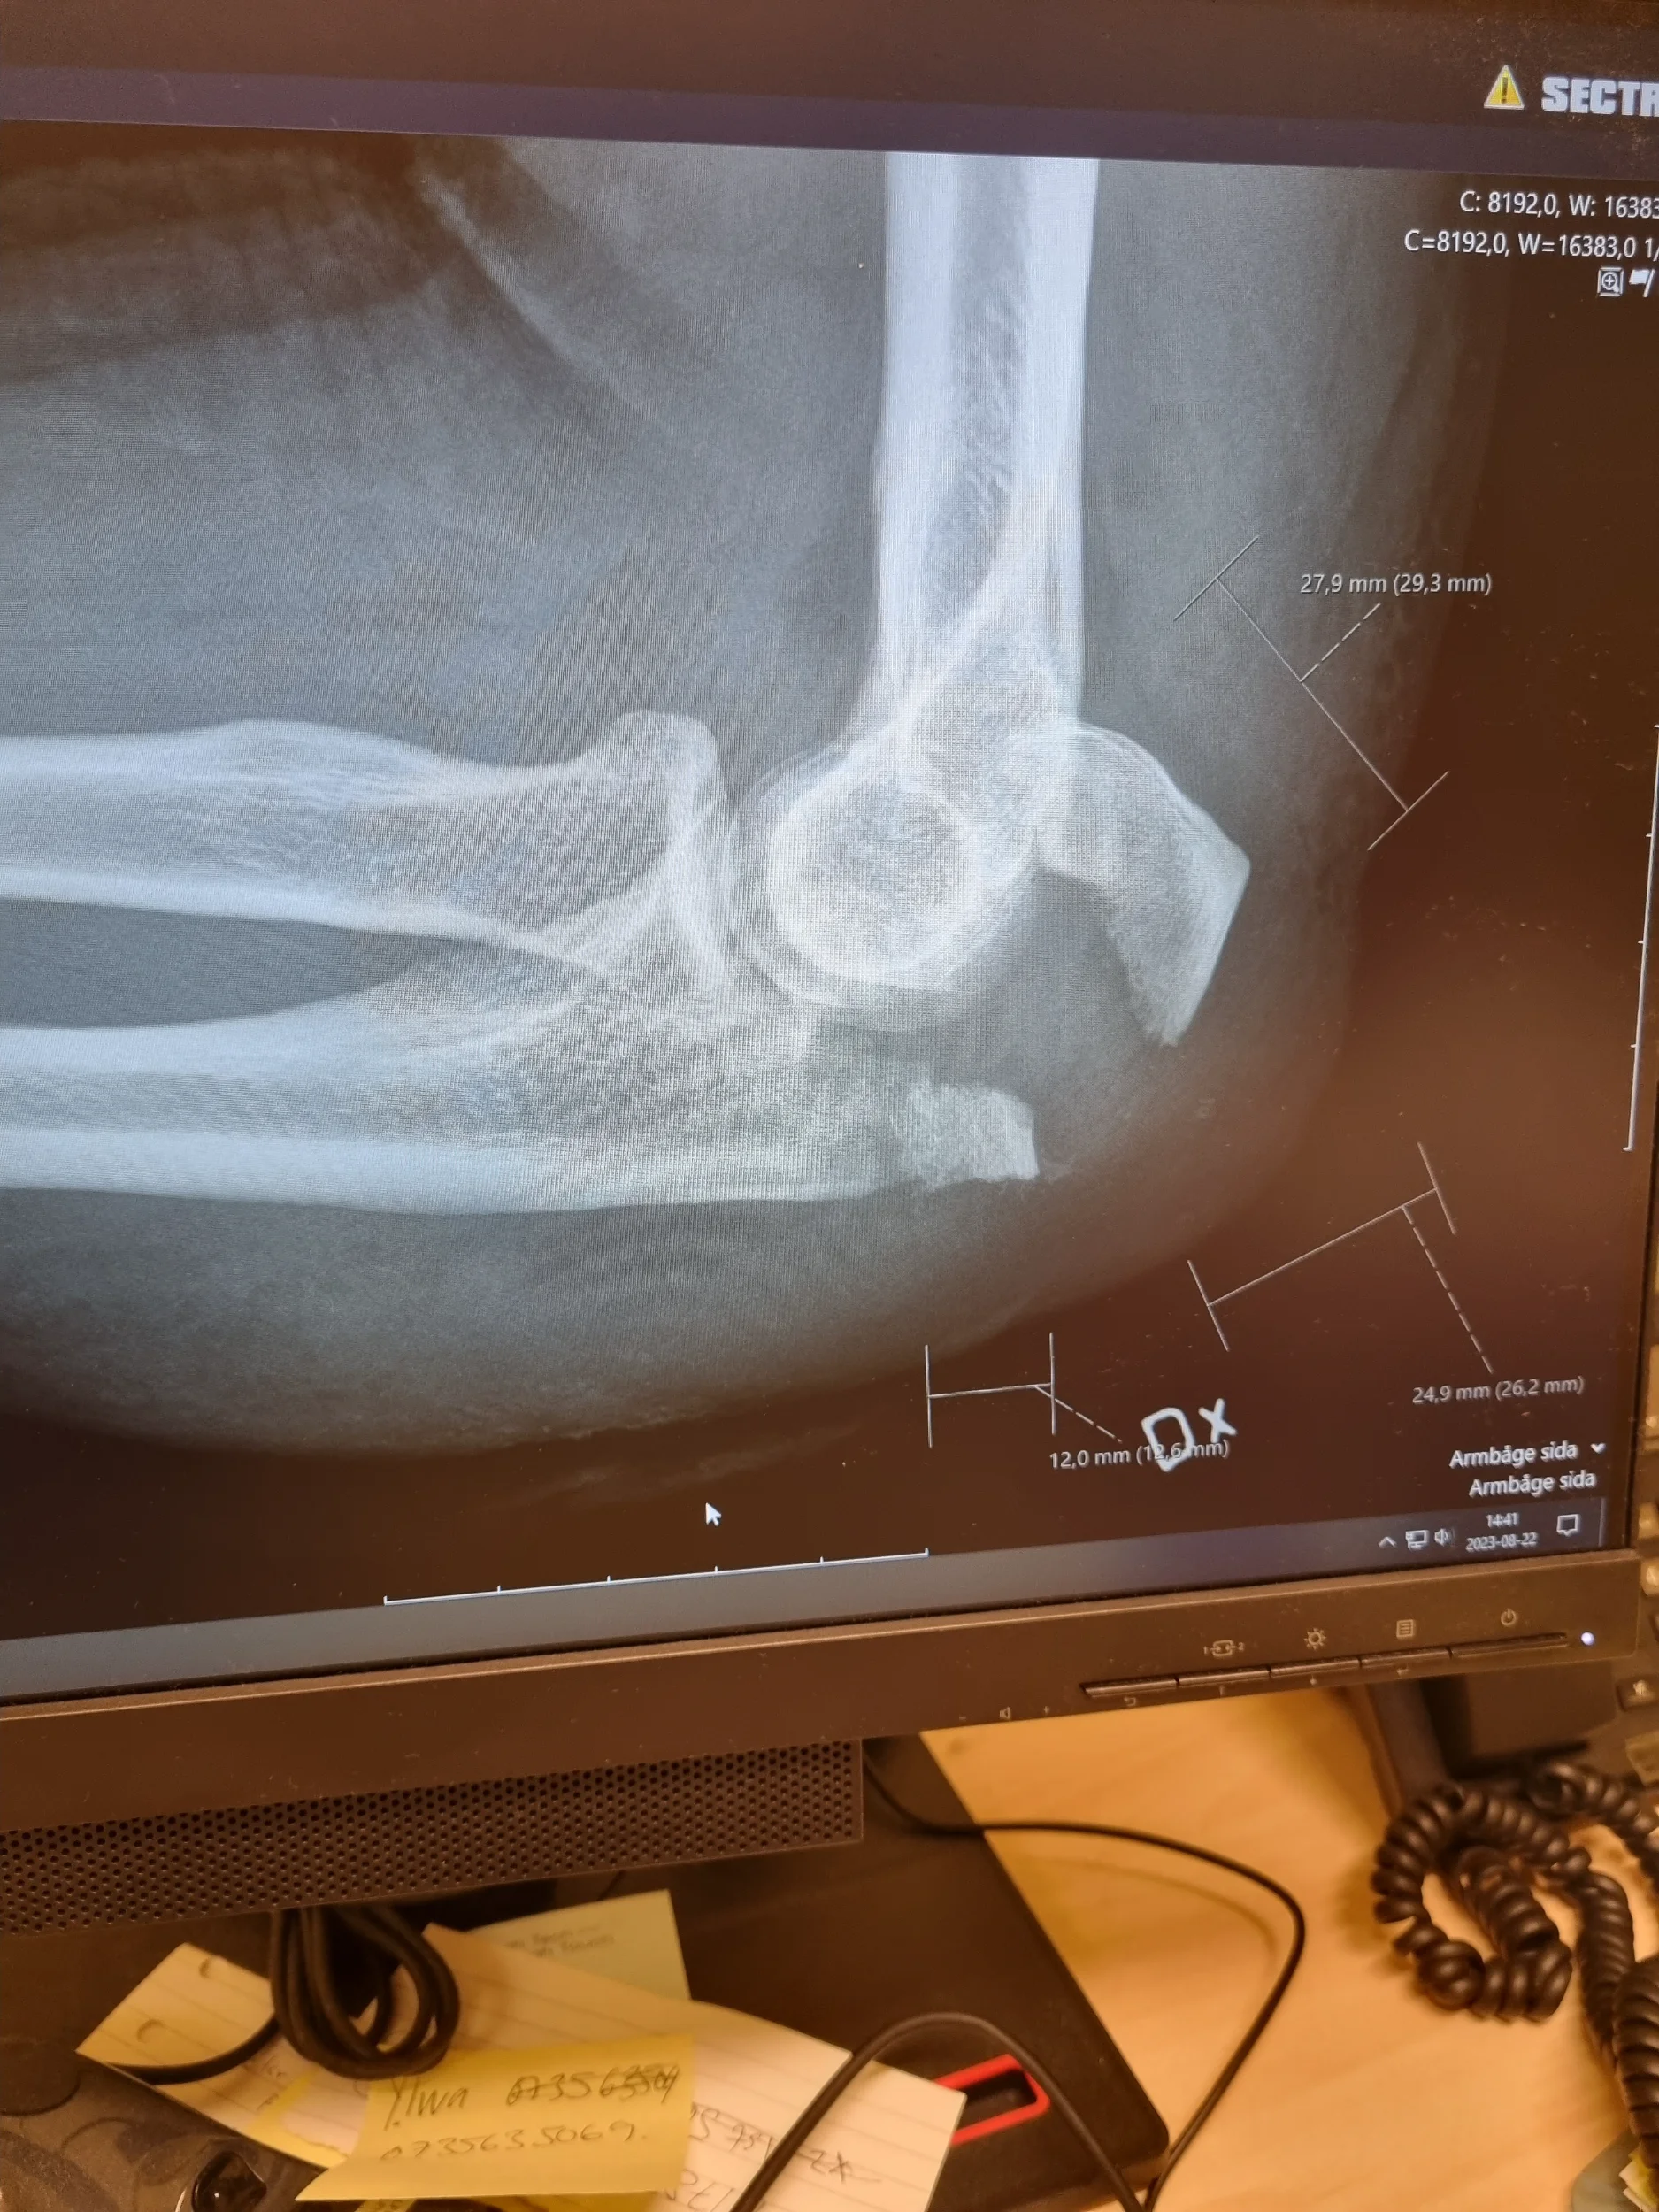

Är MTB värt skadorna??

Jeff Barber redovisar sin digra skadejournal och frågar om mtb är värt det? vad säger braintrusten på happy en fredagkväll??